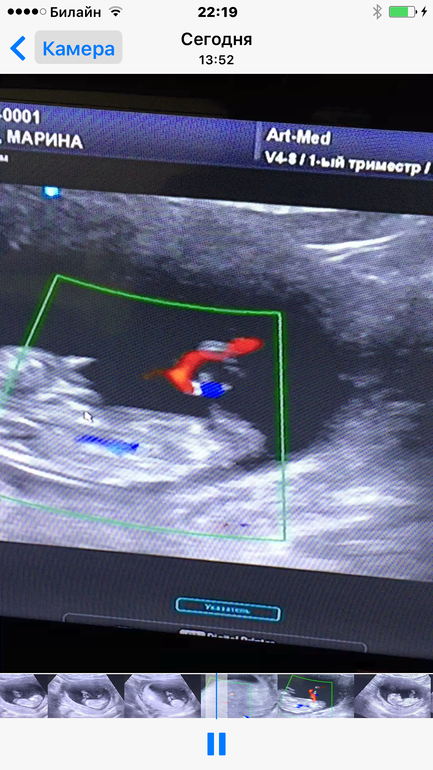

УЗИ, КТГ, доплерСегодня были на скрининге в арт-мед. Тттт с крошкой все хорошо! Мы подрастаем и очень активно себя ведем. Все показатили в норме, поставили нам 11 недель и 3 дня. Но спросив про пол ребенка , меня огорошили ДЕВОЧКА!!! Но ведь по крови прогнозировали мальчика???

Мне кажется парень будет, косточка больше вверх, а у девочек больше параллельна спинке или вниз смотрит.